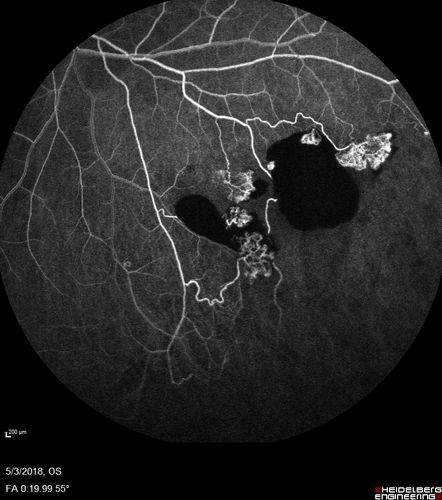

Coats' Disease -51 year old asymptomatic male

20/20 vision - had laser to non-perfusion because of proliferation.